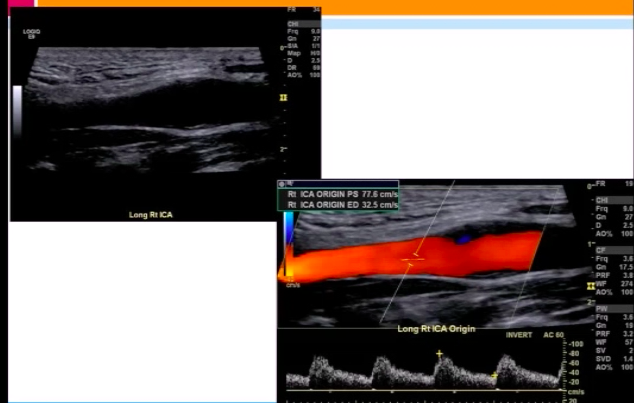

Patient has Lt ICA 100% occlusion. Rt carotid system shown below. PSV = 208 cm/s in proximal Rt ICA.

Most likely diagnosis?

mild Rt ICA stenosis (<50%)

since Lt ICA is 100% occluded, there should be elevated Rt CCA velocities (CCFA*)

plaque in proximal Rt ICA is <<50% ⇒ elevated velocities across Rt ICA are likely due to CCFA

*CCFA = compensatory carotid flow augmentation